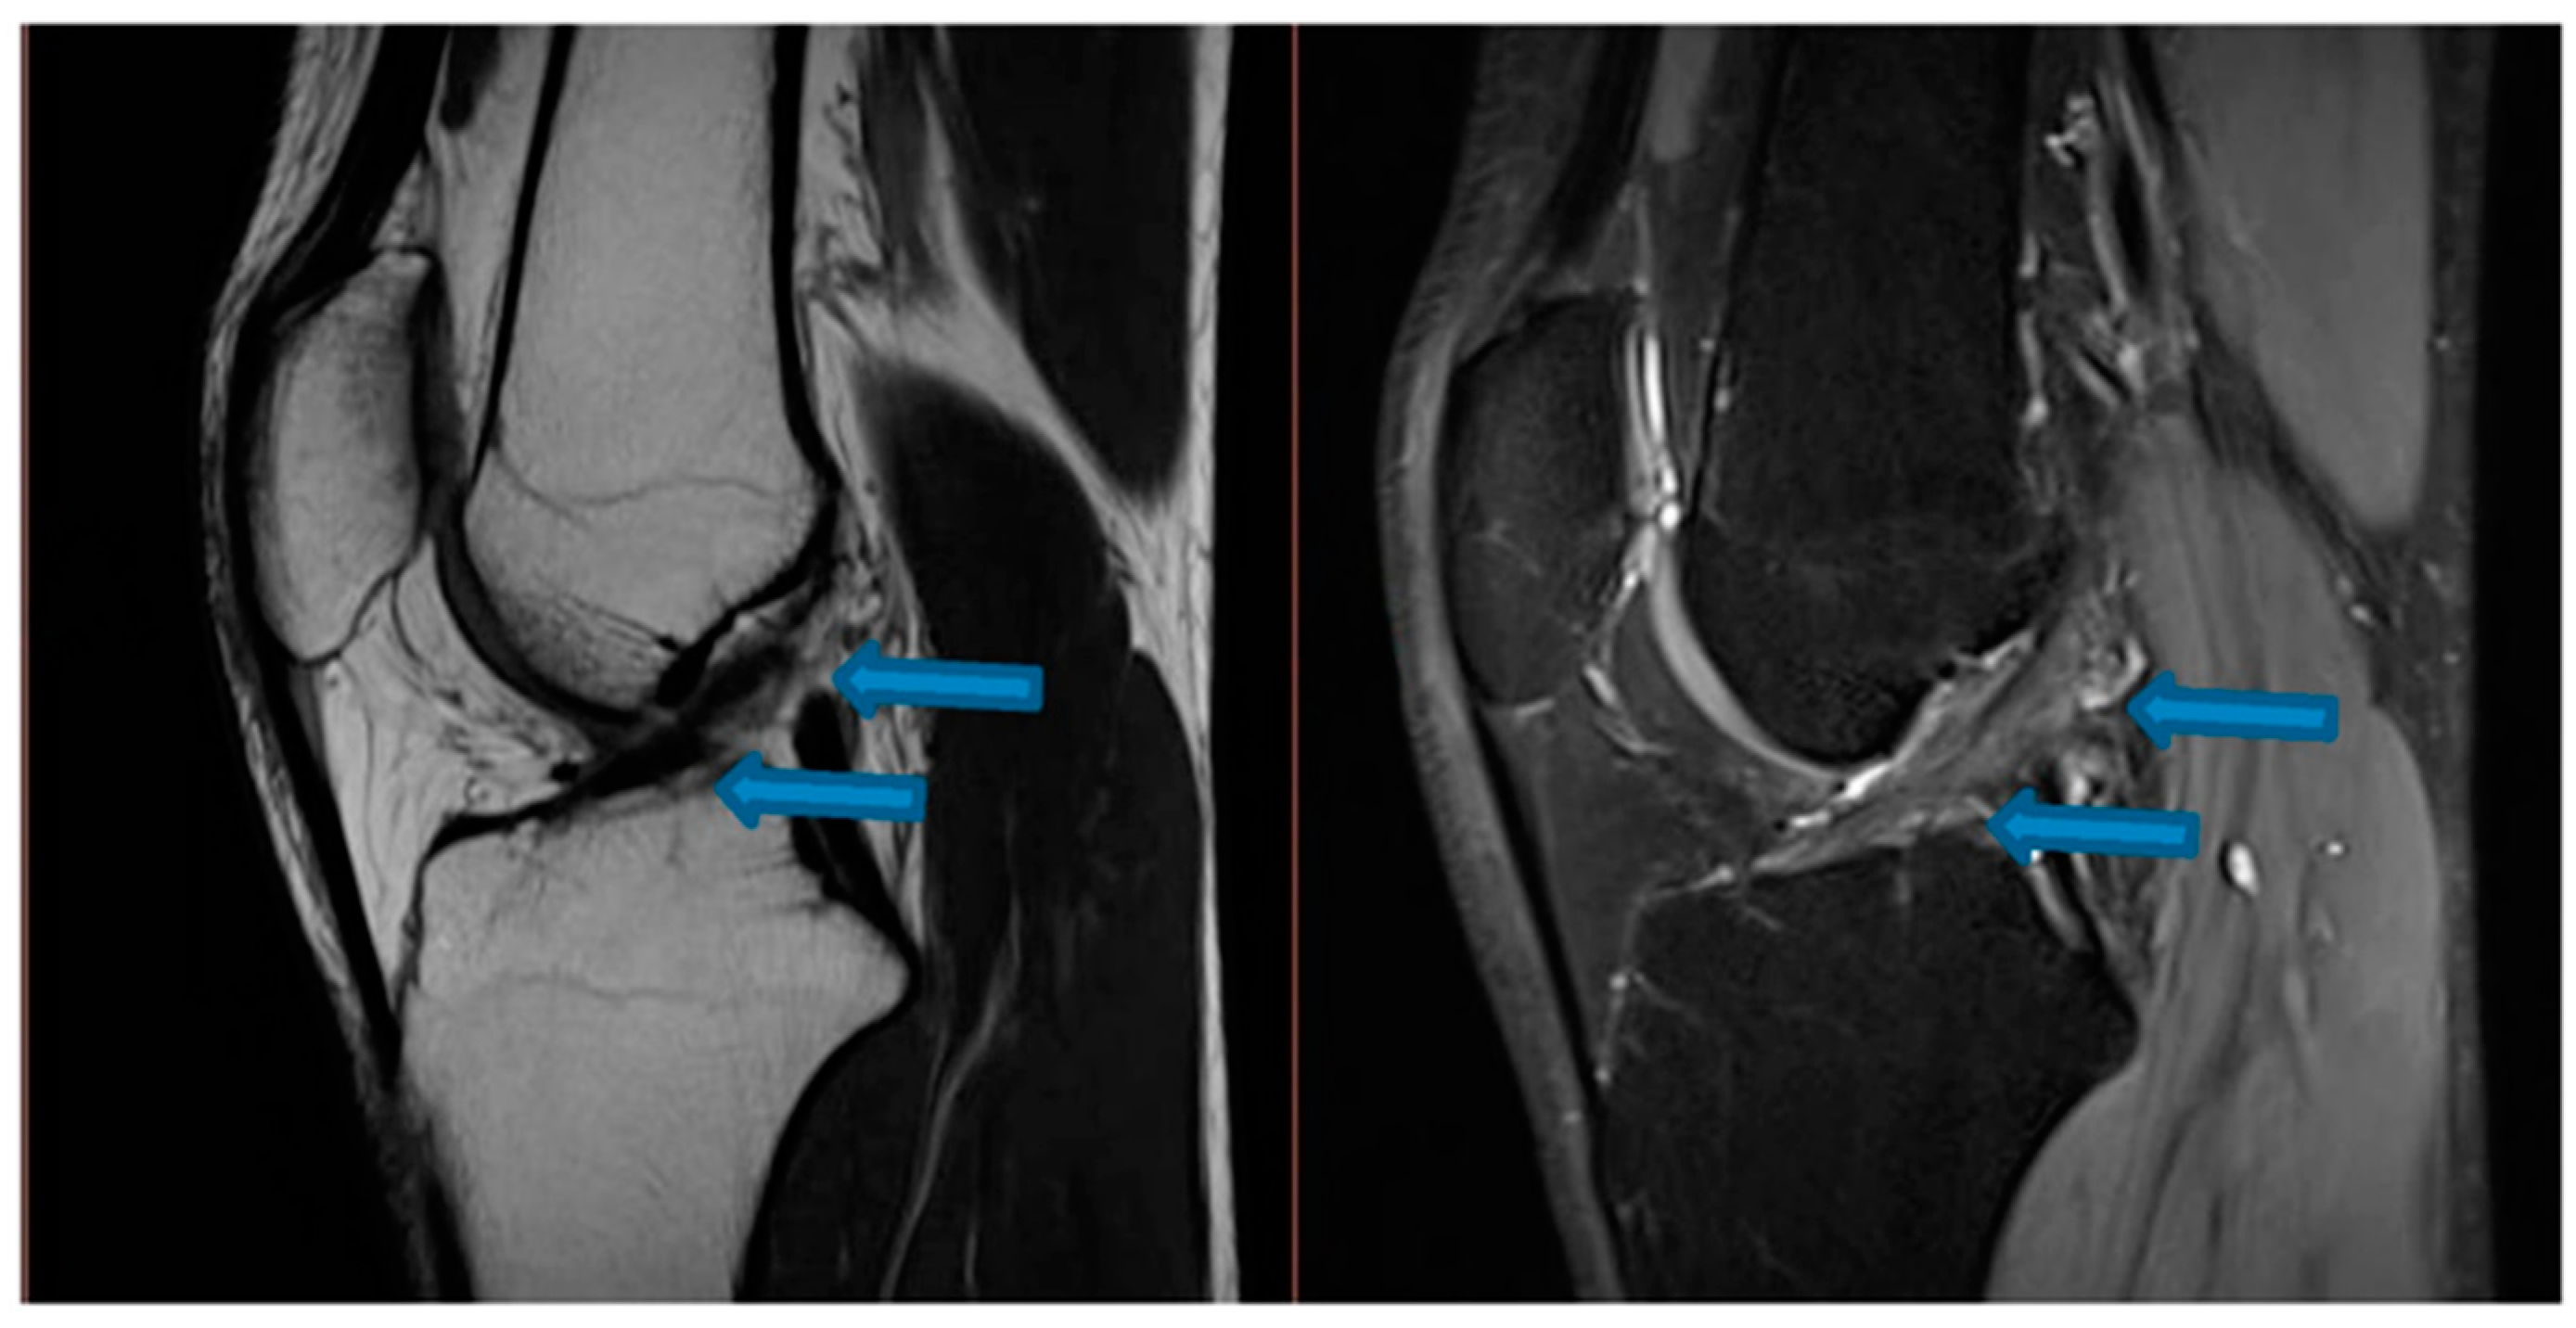

| 9 November 2020 | MRI scans demonstrating signs of partial ACL healing |

| 14 August 2021 | MRI scans demonstrating signs of complete ACL healing |

| 24 December 2021 | MRI scans confirming signs of complete ACL, MCL and medial meniscus healing |